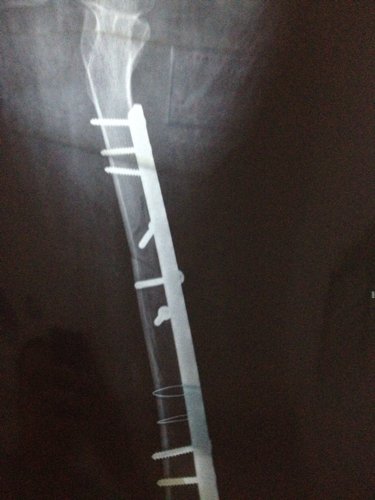

你好医生!左腿原来有小儿麻痹证,就在上个月11号不小心跌倒骨折13号做手术加钢板!现在在家休养 现 你好医生!左腿原来有小儿麻痹证,就在上个月11号不小心跌倒骨折13号做手术加钢板!现在在家休养。现在腰很痛?是怎么回事,有过性生活。现在简单吃两种药?请问医生像我这种情况会不会很难恢复原来那样?是不是还要吃些什么?还有要不要外敷些什么?还要腰很痛怎么办,谢谢! 点击展开 匿名用户 2014-04-08 09:50 为您推荐: 其他回答 病情分析: 你好,考虑是恢复期间的应急反应。 指导意见: 可以多食瘦肉、鱼、鸡蛋、牛奶、豆类食品以及新鲜蔬菜、水果等,注意逐渐恢复锻炼。 独水凡_xjeq 2014-04-08 10:51 相关问题 你好、请问:左小腿骨折做手术取钢板后可以同房吗?同房有影响吗?还是需要等的话要多久? 骨博士你好,我膝盖上面一点点骨折了,已经八个月了能取出钢板了吗 骑电动车把左股骨颈摔骨折了,而且左腿是小儿麻痹,女,年龄五十四岁,在家静养能康复吗?有什么好办法吗

你好医生!左腿原来有小儿麻痹证,就在上个月11号不小心跌倒骨折13号做手术加钢板!现在在家休养。现在腰很痛?是怎么回事,有过性生活。现在简单吃两种药?请问医生像我这种情况会不会很难恢复原来那样?是不是还要吃些什么?还有要不要外敷些什么?还要腰很痛怎么办,谢谢!